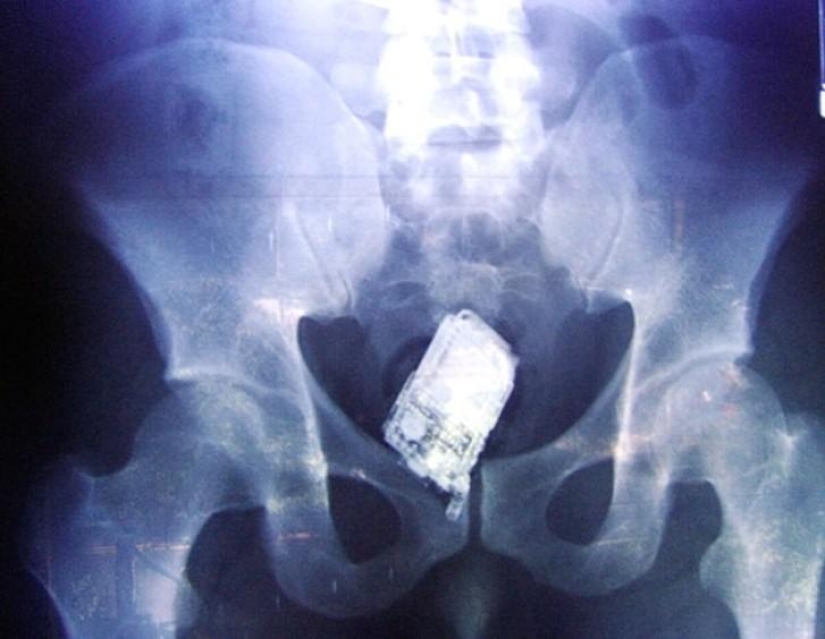

20. Mobile phone.